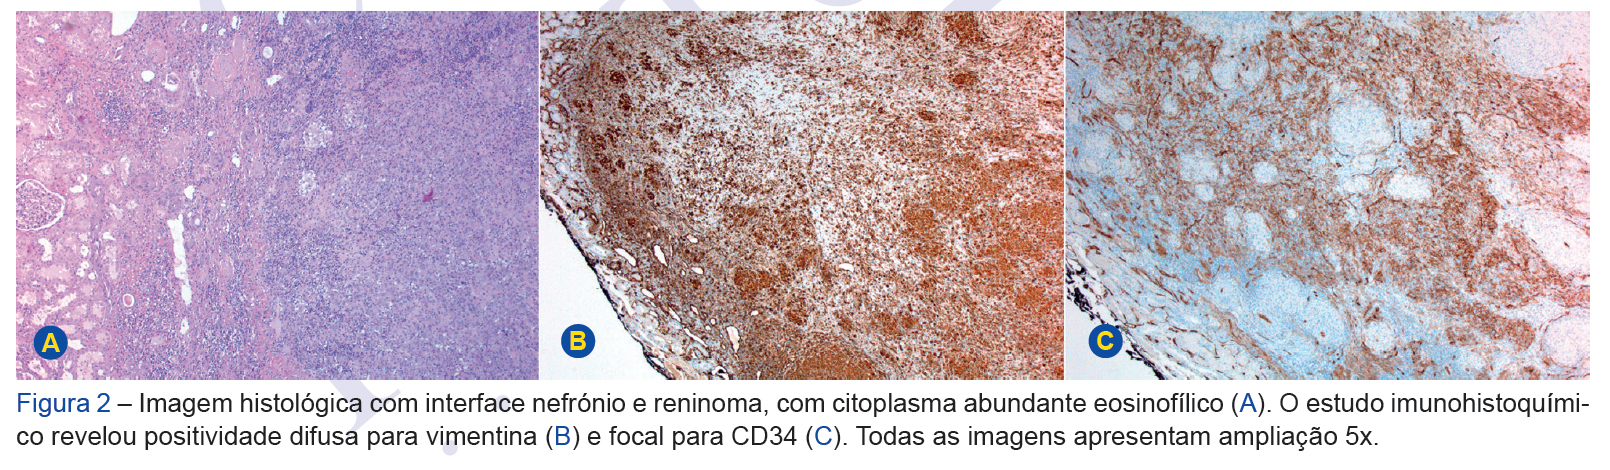

Juxtaglomerular tumours are rare causes of secondary hypertension. They typically present with difficult-to-manage hypertension, hypokalemia, hyperreninemia and s...